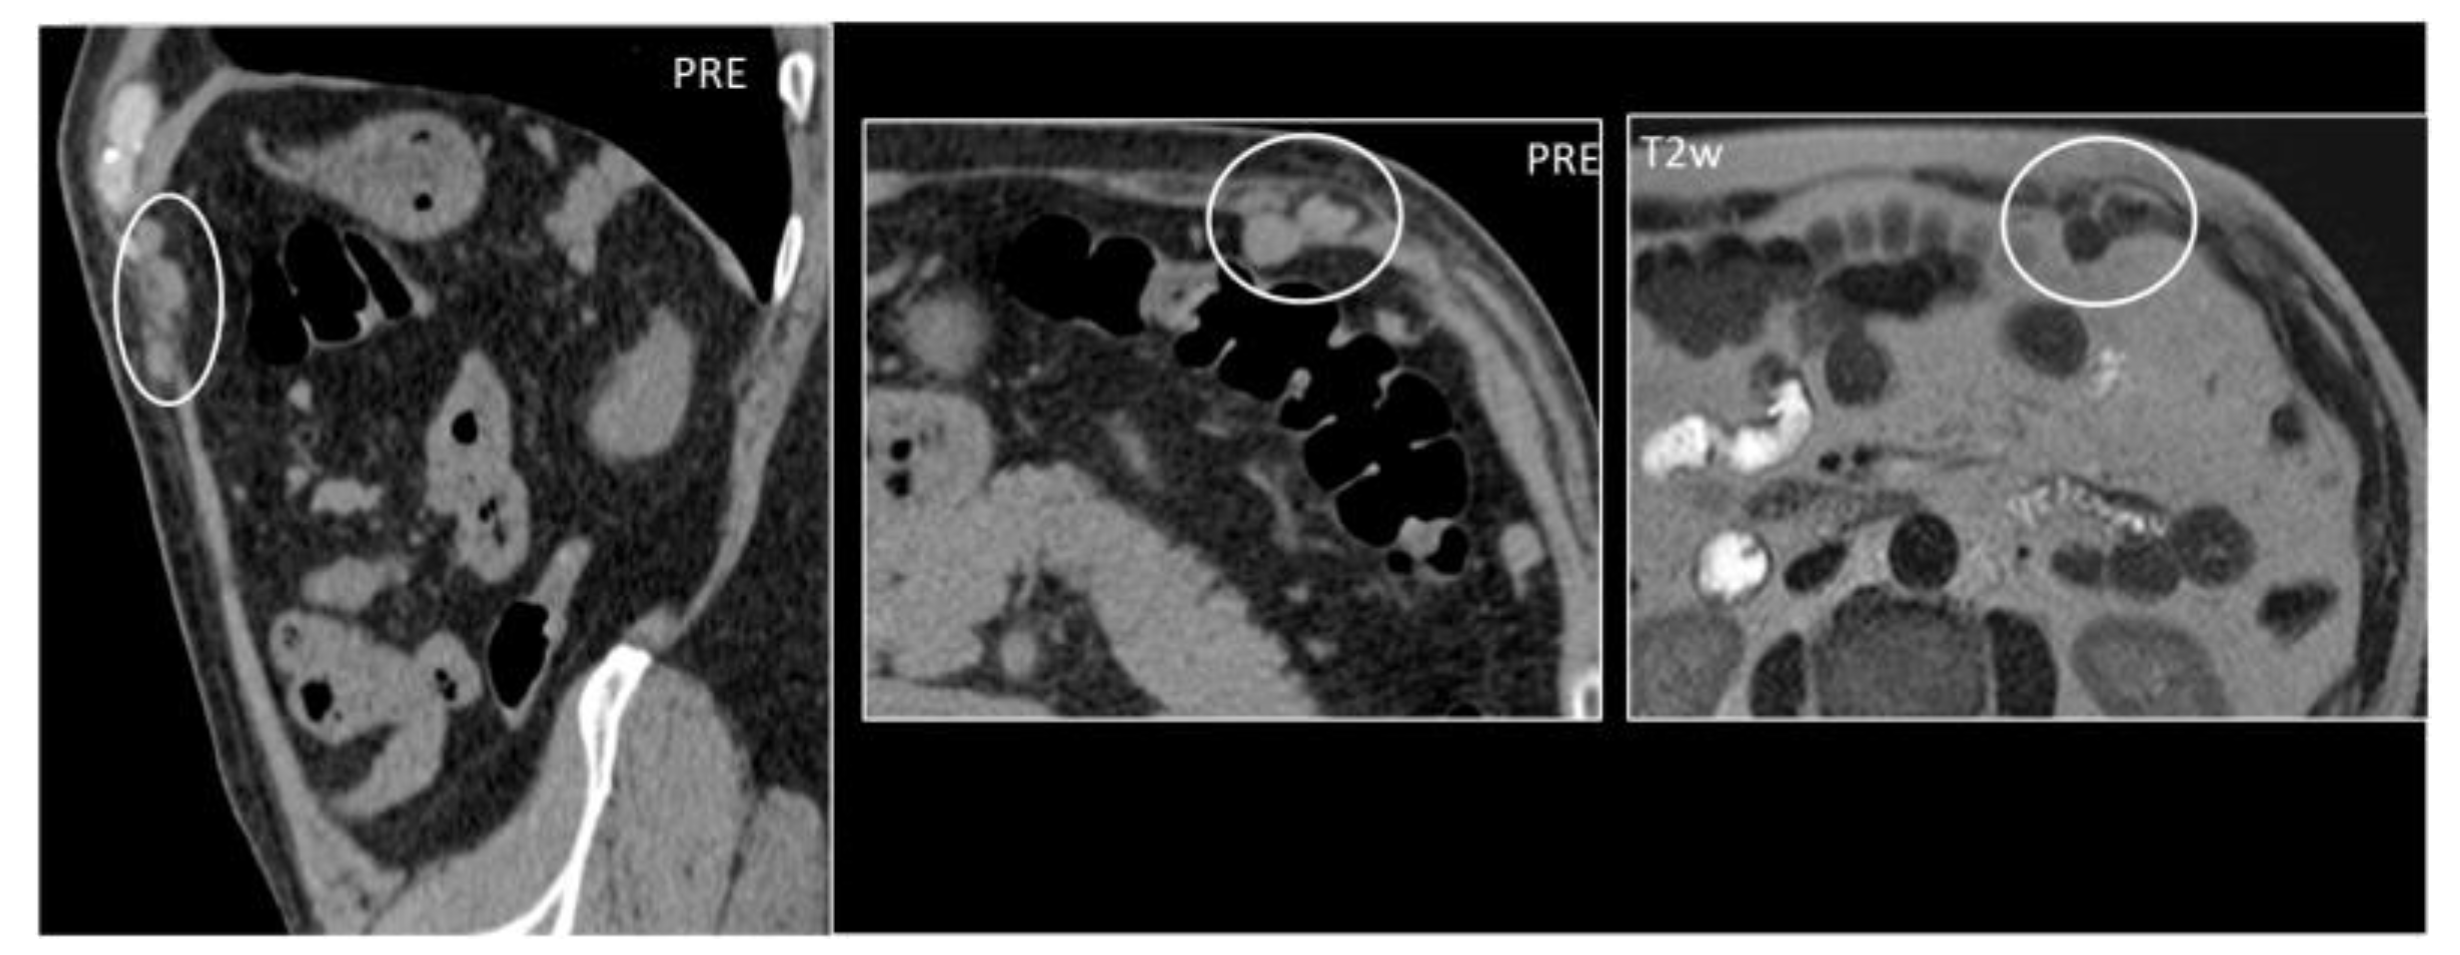

Figure 16. A 59-year-old woman who underwent splenectomy some years prior. During a CT scan, new, rounded masses (circles) were found along the peritoneum and the left rectus abdominis muscle. These formations show parenchymal attenuation on CT (pictures 1 and 2) and share the same T2 intensity as the spleen. These lesions were later characterized as splenosis.